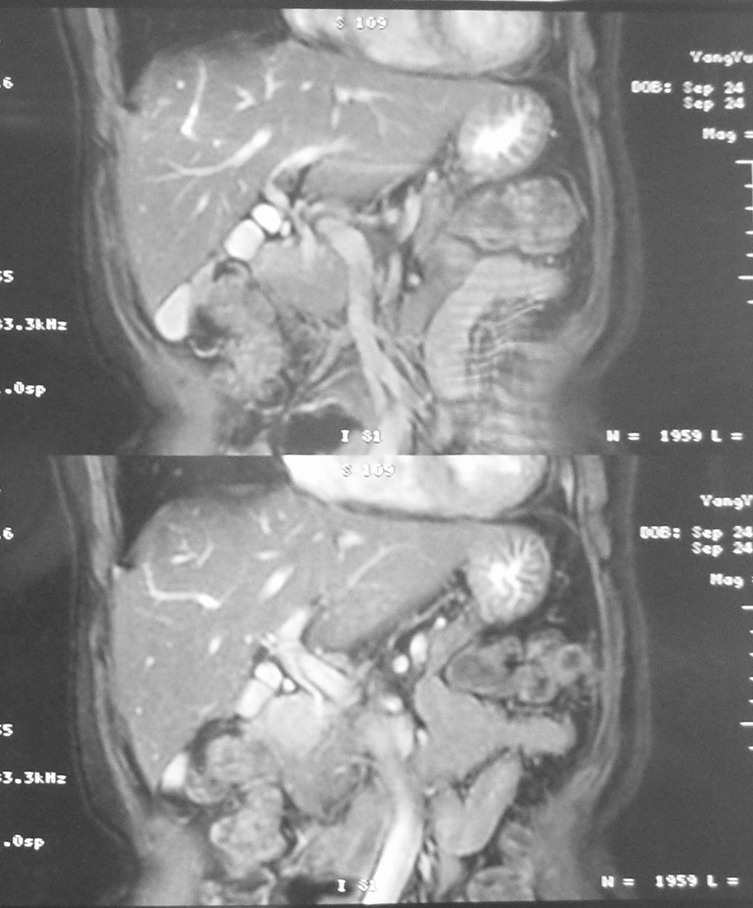

标题: MRI2066:腹膜后占位,请会诊,CT18531近期扫描图像

无明显不适,体检发现,

mri基本排除血管类肿瘤,明显强化说明极富血供,临床无症状,考虑胰岛细胞瘤可能大。

强化明显,并见有血管与之相连;考虑巨淋巴增生症.

极富血供的占位性病变,首先考虑良性,期待结果。